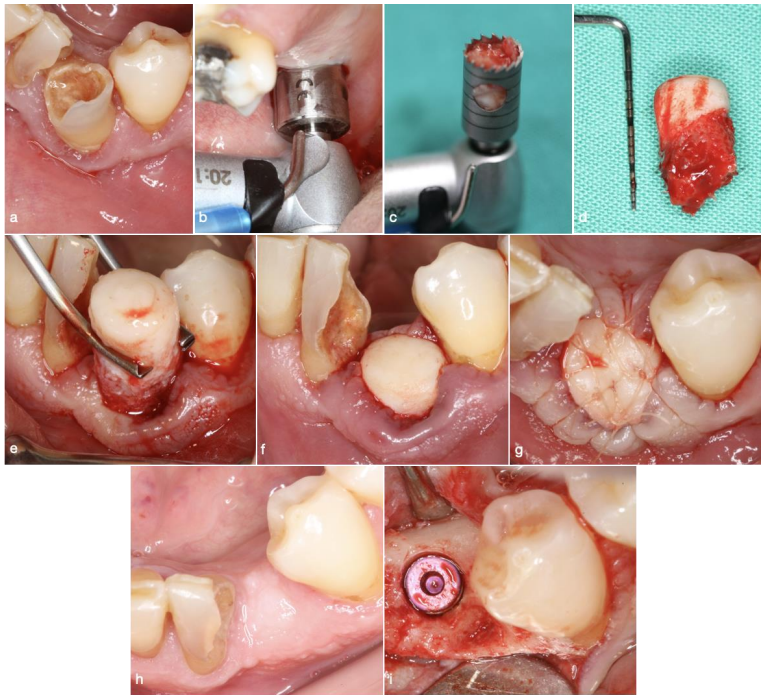

Patients were scanned using the Newtom VGI CBCT machine, with imaging conditions including 110 kv tube voltage, 2.2 to 8.30 mA tube current, 15 x 15 cm field of view, and 0.3mm voxel size. Projection data were collected with a device rotating 360 degrees around patients for 18 seconds. Images were evaluated using the NNT 5.6 software, which re-oriented the images according to three planes: horizontal, vertical, and mesio-distal. T1 and T2 DICOM images were imported and loaded simultaneously into the ITK-snap software, with T1 being the pre-operative CBCT and T2 four months post-operatively. The two CBCT scans were superimposed using the transform and general registration modules, and alignment was manually checked after registration in the three spatial planes. The software allowed a direct comparison of the two scans while maintaining the same alignment.

Figure 4 Screenshot of the ITK-Snap software showing the superimposition of the pre-op and post-op CBCT images in the 3 spatial planes.

The study used a cross-sectional 2D slice to measure bone and soft tissue. Bone measurements involved calculating the difference between bone peak levels (T2 – T1) in mm, bucco-lingual width at three different levels (2, 4, and 6 mm) from the most coronal point of the buccal bone, and the difference between T1 and T2 at these levels in mm and %. Soft tissue measurements included the thickness of the mucosa on the buccal side at 2 mm from the most coronal point of the buccal bone, and the difference between T1 and T2 thickness in mm.

Figure 5 Cross sectional images showing the superimposition of T1 and T2. 2D measurements were made (a) Vertical variation of the bone peak between T1 and T2 (b) bucco-lingual width is measured at 3 different levels on both T1 and T2 images (c) thickness of the buccal mucosa at 2 different levels on both T1 and T2 images.